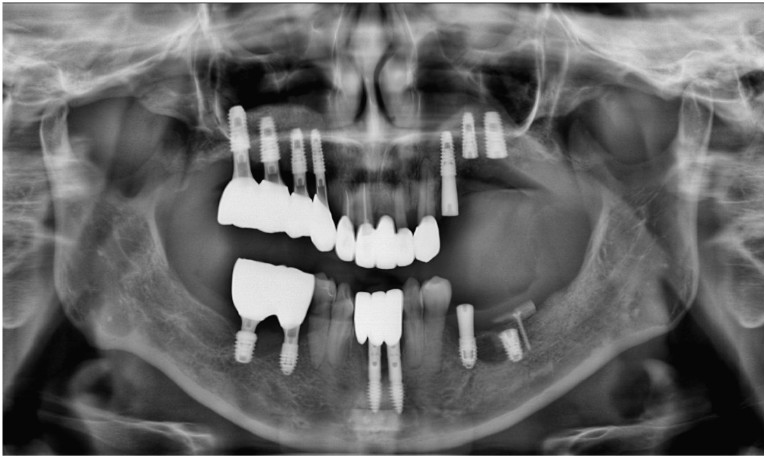

먼저 구강 내를

확인해 보았더니

다수 치아의 상실로 인해

치아의 배열이 흐트러져 있고,

잔존 치아들도

동요도가 심한 상태였는데요.

정밀한 검사를 위해

파노라마 사진을

촬영해 보았더니

만성 치주염으로 인해

다수 치아 상실과

심각한 골소실이 보였으며

이로 인해 양측 어금니 부위의

교합 및 수직 고경이 소실된 상태였습니다.